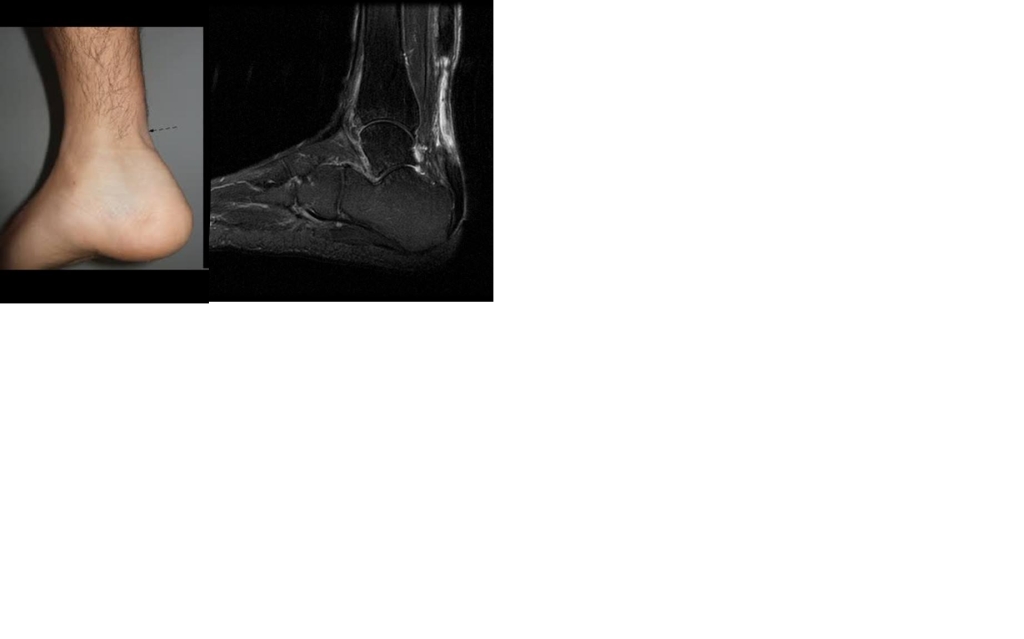

achilles tendon